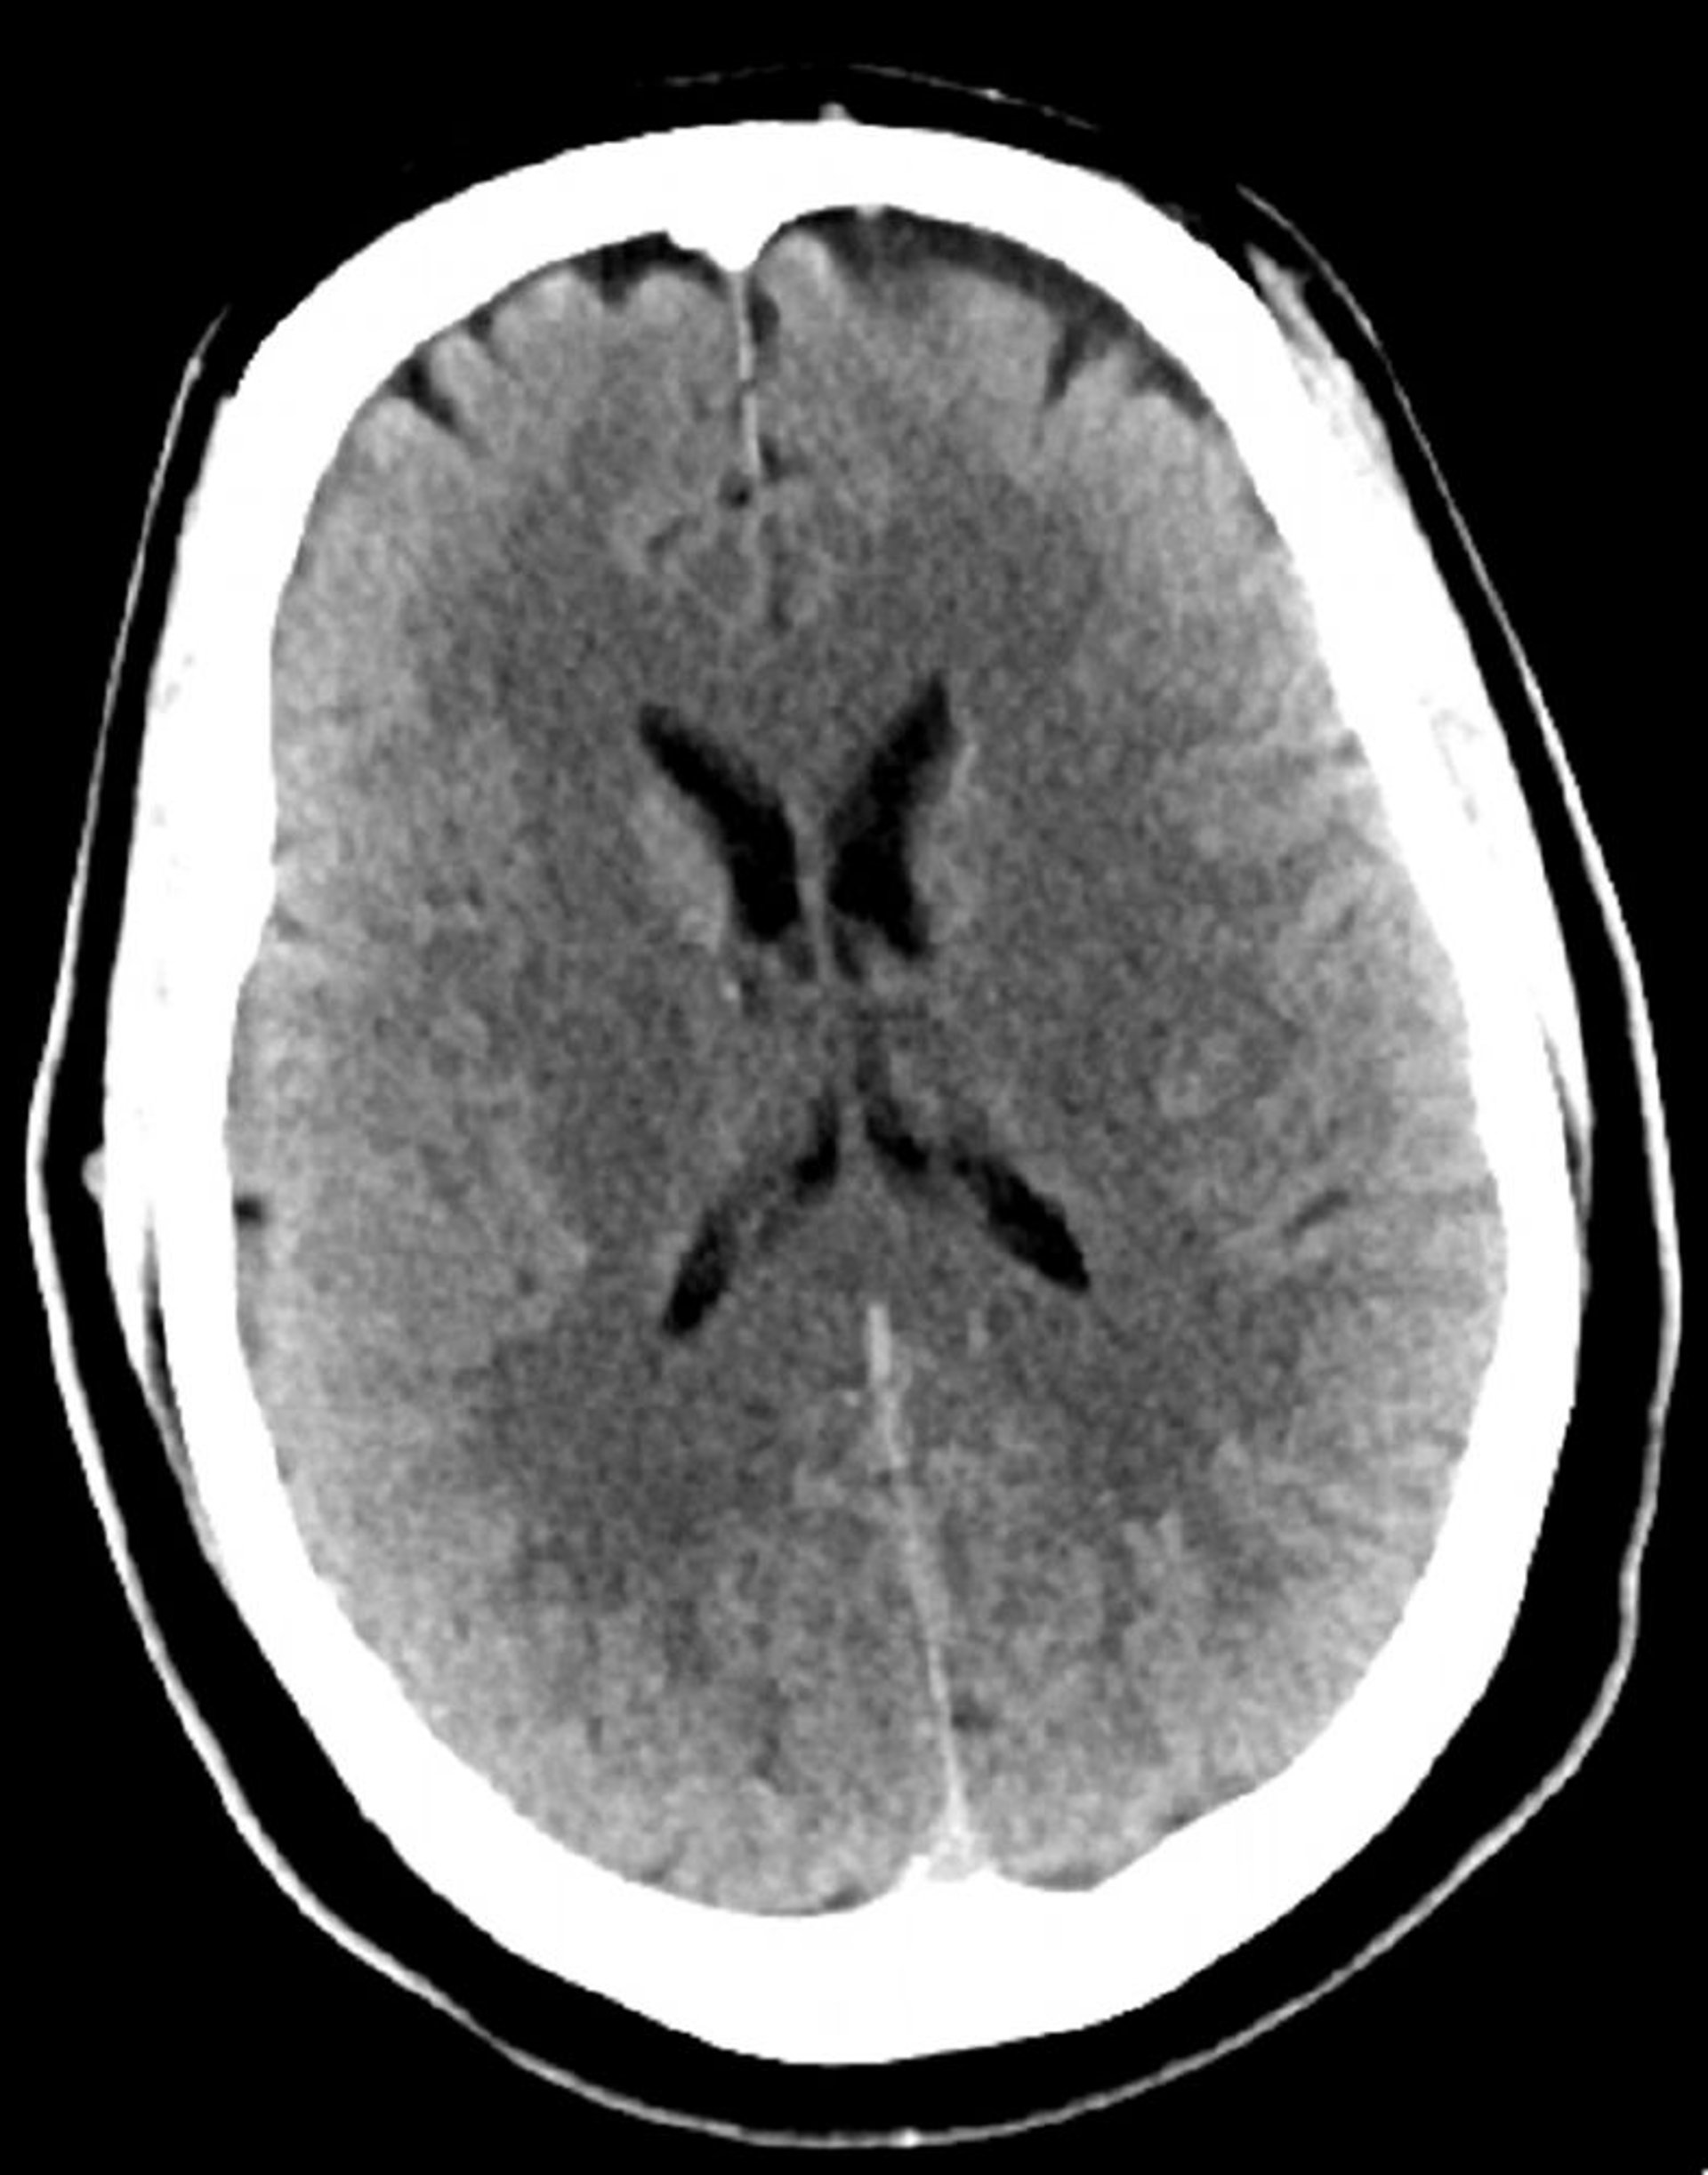

Стандартное КТ-сканирование головы (взрослые, возраст 30 лет) – слайд 4

Это изображение – обычный КТ-снимок головы взрослого человека в возрасте 30 лет. Ни внутри паренхимы мозга, ни вне ее не наблюдается накопления жидкости или кровоизлияния. Дифференцировка серого и белого вещества сохраняется. Размер желудочков и характеристики борозд в норме.